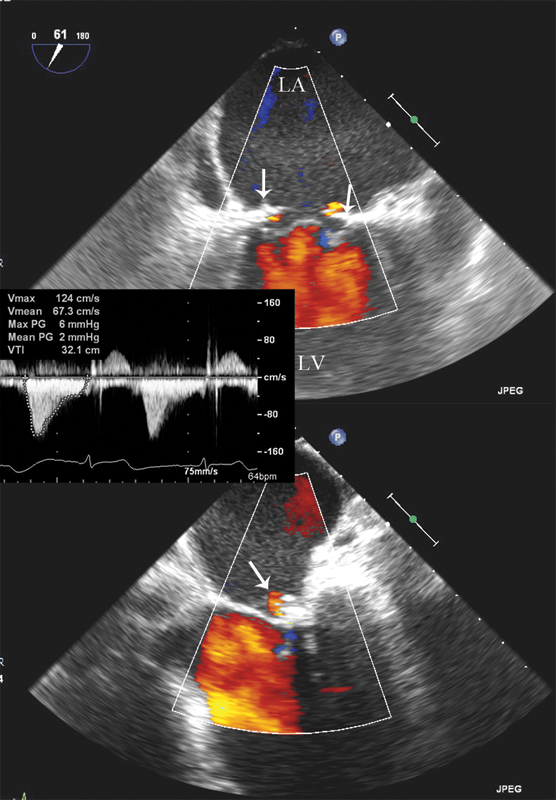

فحوصات تشخيصية لبعض امراض القلب والشرايين التاجية